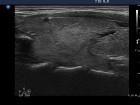

Follow-up examinations (rows from 1st to 8th):

1. The patient initially presented with a large thyroid, therefore we suggested definitive therapy.

2. Note the relation between volume, echogenicity, vascularization and hormone levels.